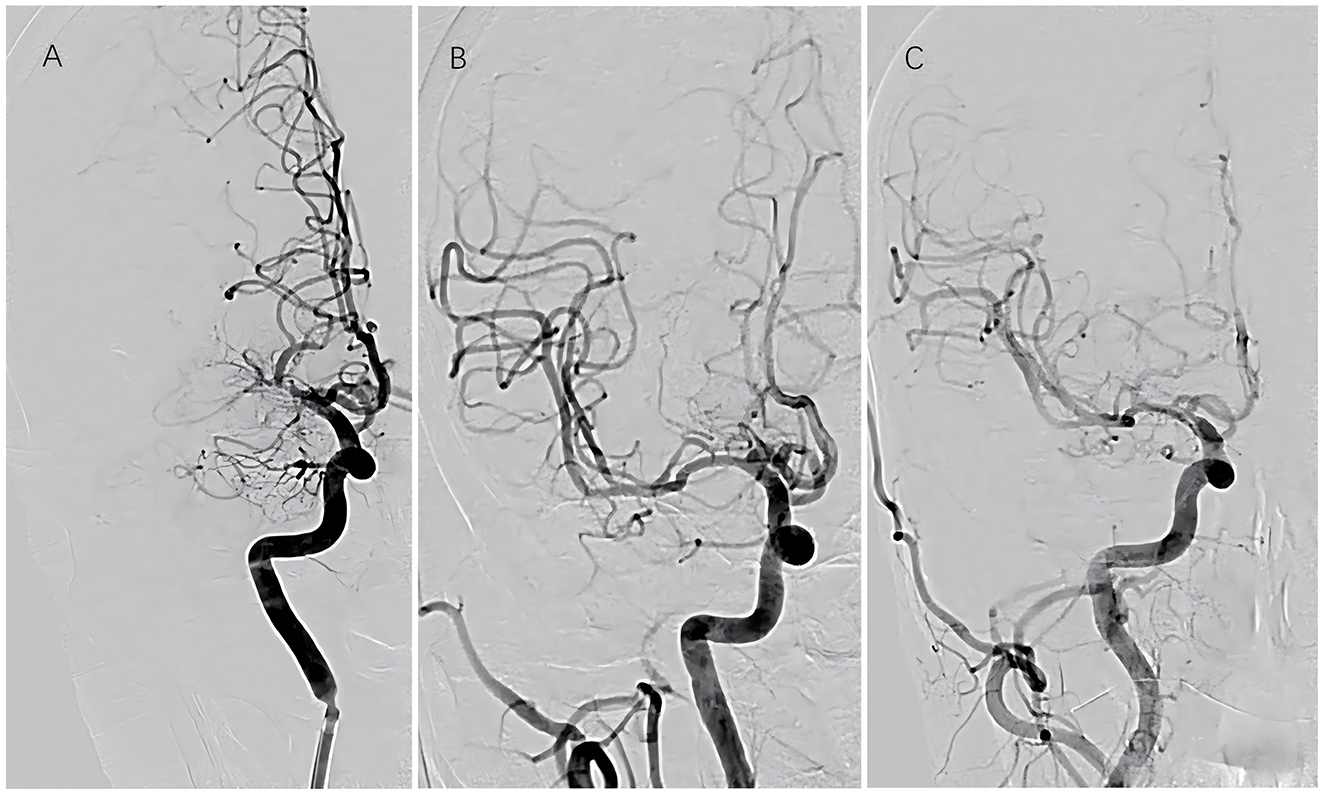

Figure 2

Sequential vascular imaging of recanalized segment. (A) Preoperative angiography; (B) immediate postoperative angiography; (C) angiographic evaluation at 6-month follow-up.

Among the 29 patients who underwent interventional surgery, successful recanalization was achieved in 26 cases, while three procedures were deemed unsuccessful. All patients who underwent successful recanalization demonstrated residual stenosis of < 10% immediately postoperatively. According to the TICI grading system, four patients achieved grade 2b perfusion and 22 achieved grade 3 perfusion. Recanalization was achieved in 11 cases of left MCAO and 15 cases of right MCAO. Of the surgical cases, balloon angioplasty alone was performed in 13 patients, while 13 required stent implantation (nine with self-expanding stents and four with balloon-expandable stents). No cases of intraoperative hemorrhage were observed. Immediate postoperative cranial CT identified minor contrast extravasation in five patients; however, no worsening of neurological deficits occurred. Perforator-related complications were documented in four cases, including dysarthria (n = 1), limb numbness (n = 2), and decreased muscle strength (n = 1), all of whom recovered satisfactorily. No embolic events were reported. At the 6-month follow-up, two patients developed new mild cerebral infarctions: one due to re-occlusion and one secondary to a perforator-related event. Additionally, three patients exhibited > 50% restenosis (Figures 1, 2). In the medication group, three patients experienced new cerebral infarctions during the follow-up period, all categorized as minor strokes. One additional patient experienced a TIA, which was effectively managed with pharmacological treatment.